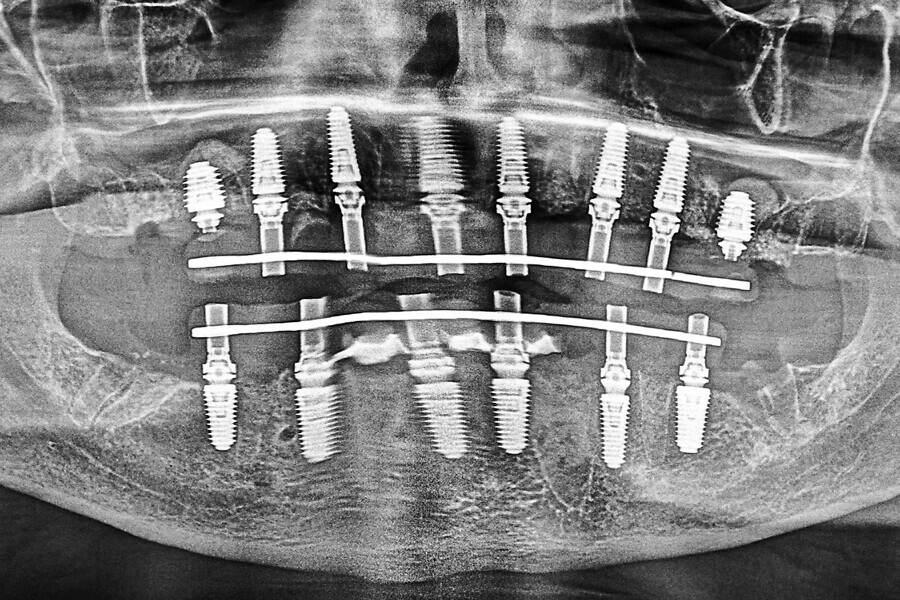

Fig. 16a: Panoramic radiograph showing printed restorations secured with Grammetry Vortex LA VIS screws.

Fig. 17a: Final panoramic radiograph confirming seating of the zirconia restorations.

The data collected was sent through a scanning software portal (Medit Scan for Clinics) to the dental laboratory with requested changes for correction of the desired smile design. Utilising advanced planning features in the design software (exocad), the midline and tooth size changes were corrected. 3D-printed maxillary and mandibular PMMA restorations were used for try-in using the direct-to-MUA screws (Vortex LA VIS; Fig. 16a). Fit, phonetics, aesthetics and occlusion were evaluated and confirmed using digital articulation (OccluSense; Fig. 16b). The patient was extremely satisfied with the printed try-ins. Since no adjustments were required, the patient was allowed to leave with the printed try-ins as new provisional restorations made from extra-strong resin. The new provisional restorations were worn for ten days to confirm form and function. The final shade was chosen, and metal-free monolithic zirconia restorations were then fabricated by the laboratory.

The final restorations were passively and accurately seated ten days later uneventfully using Vortex LA VIS screws. Confirmation records were taken with photographs, radiographs and digital articulation to recheck fit, function, phonetics and occlusion (Fig. 17a). The patient was extremely satisfied with his final restorations, describing the process as life-changing and surprisingly fast in comparison with what he had heard about full-mouth implant therapy. He was especially pleased with the speed at which the final process was able to be completed (Figs. 17b & c).